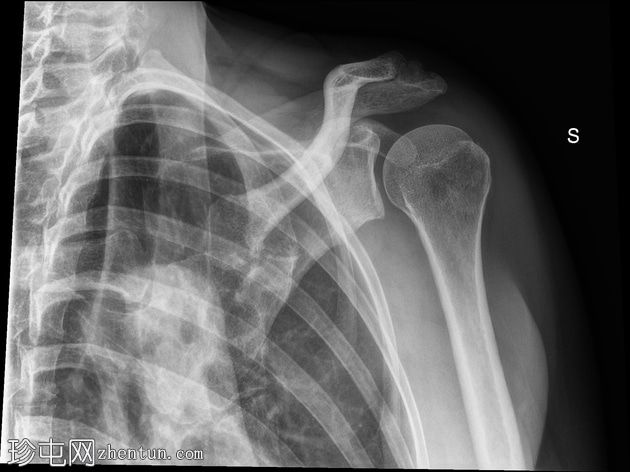

X线片

正位 -

内旋位

可见肱骨头周围、三角肌腱和冈上肌腱之间有钙化沉积物,呈致密均匀的阴影。